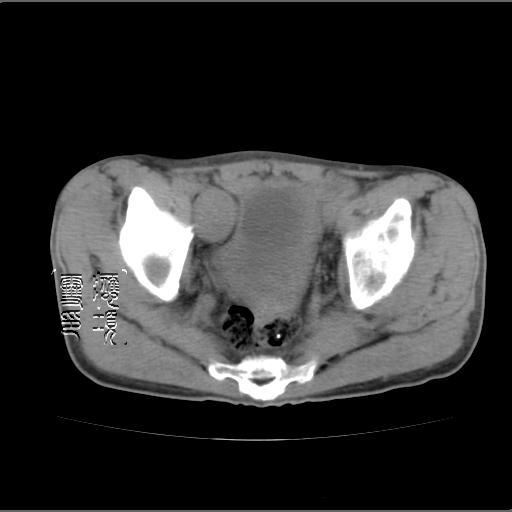

以下是引用余辉在2007-4-20 20:03:00的发言:[br]没头绪,猜一个吧,距离血管鞘近,就猜神经鞘瘤,中心部分变性囊变,另外请哪能位老师指点腹直肌后方及后外方强化物是何

以下是引用dyqct在2007-4-20 20:51:00的发言:[br]考虑:1、右侧膀胱外上方实性富血管性肿瘤(神经鞘膜瘤?纤维瘤?巨淋巴结增生症?)[br] 2、请标识需要解释的地方。

以下是引用aa13877358820在2007-4-21 7:01:00的发言:[br]隐睾?